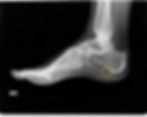

La spina calcaneare, come abbiamo accennato prima, รจ una protuberanza ossea che si forma a livello del Calcagno. Solitamente quando il paziente soffre di fascite plantare viene prescritta dal medico una radiografia per verificare se vi รจ o no la presenza di questa spina.

Nellโimmaginario comune infatti vi รจ lโidea che questa vada tolta, sciolta, grattata via, perchรฉ causa del dolore. Nella realtร questa รจ una conseguenza anzichรจ una causa.

Infatti il deficit di irrorazione e la contrattura della fascia plantare possono causare, proprio a livello della sua inserzione sul calcagno, la formazione di questa piccola escrescenza ossea. Perciรฒ la spina insorge in un secondo momento, dopo diverso tempo che il piede ed in particolare la pianta segue una fisiologia alterata, non regolareร lavora male.

Spina calcaneare --> si tratta di una formazione ossea a โbeccoโ del Calcagno, proprio dove si inserisce la fascia plantare.